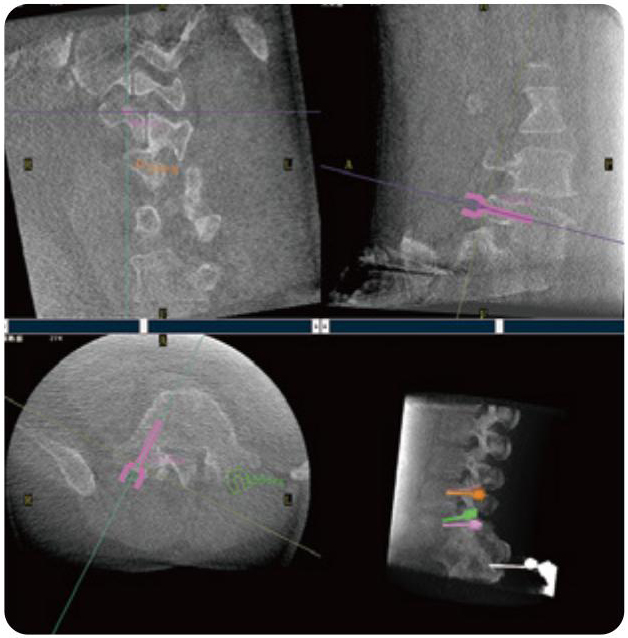

PL300B可應(yīng)用于多節(jié)段脊柱外科手術(shù),輔助醫(yī)生定位病灶部位,為脊柱外科手術(shù)(經(jīng)皮椎體成形術(shù)、椎弓根螺釘內(nèi)固定術(shù)等術(shù)式)提供術(shù)前手術(shù)流程規(guī)劃、入釘位置、角度可視化引導(dǎo),模擬仿真入釘輔助。

PL300B搭配普愛醫(yī)療自主研發(fā)生產(chǎn)的平板3D C形臂,借助一體化自適應(yīng)配準(zhǔn)( 軌跡配準(zhǔn))技術(shù),通過追蹤C(jī)形臂三維采集軌跡,自動完成圖像坐標(biāo)建立和系統(tǒng)坐標(biāo)配準(zhǔn)。配準(zhǔn)精度更高,操作步驟少,系統(tǒng)運(yùn)作效率高。